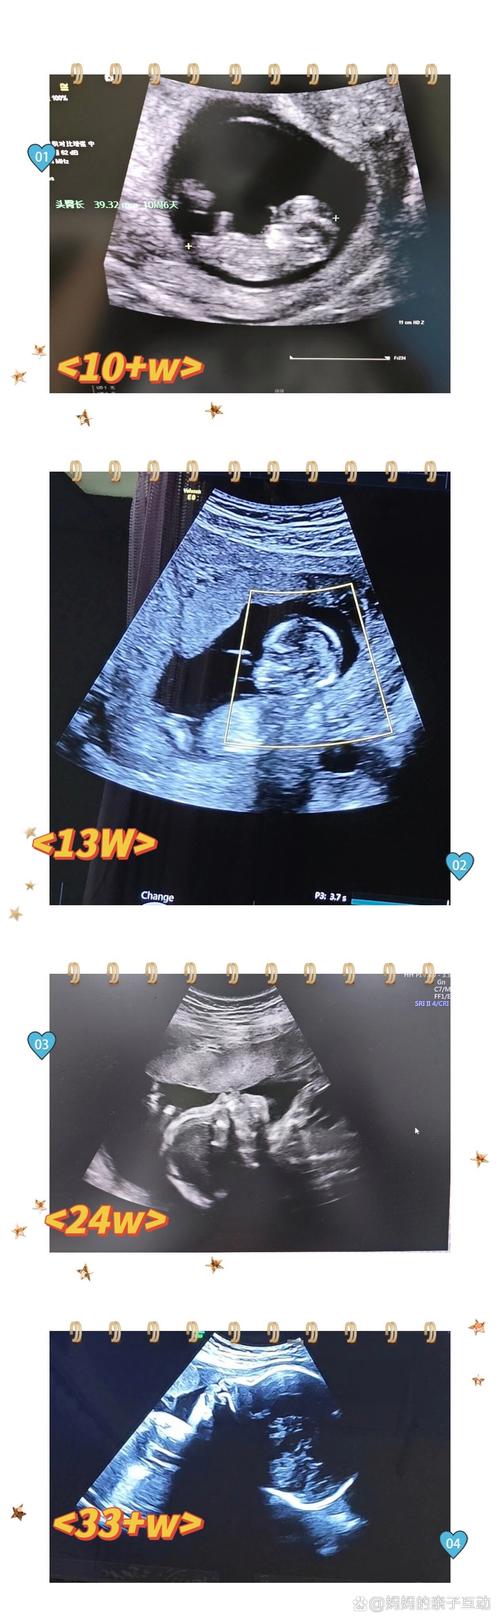

肝脾上下径比值:

(图片来源网络,侵删)- 测量方法:同时测量肝脏和脾脏在同一个切面上的最大上下径,然后计算两者的比值。

- 正常参考值:肝脏的上下径通常大于或等于脾脏的上下径,即比值 L/S ≥ 1,如果脾脏比肝脏大,可能提示肝脏有问题或存在其他情况。